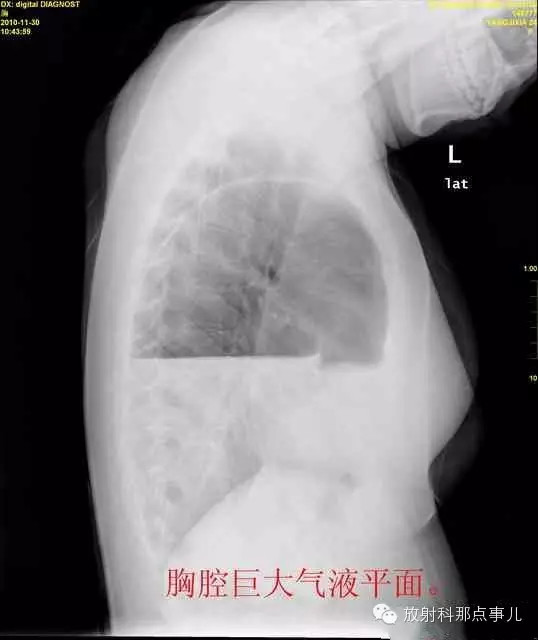

24岁,女性,腹痛渐加重并呕吐。

患者系顺产后18天产妇,产后感觉腹部疼痛不适,自认为正常反应,近两日因胸闷、腹部疼痛加剧伴呕吐来院就诊。

门诊腹部透视发现左侧胸腔巨大气液平面,为排除膈疝口服钡剂,但造影剂未见进入胃内。嘱住院,外科给予胃肠减压、补液等处理常规处理(未引流出明显气、液体)。5个半小时后再次检查,见少量造影剂进入消化道;为进一步了解情况,予泛影葡胺分别经胃管推注及口服,但均未进入胃内。当天进行外科急诊手术。

大部分胃、脾及横结肠均经过胸肋三角疝入左侧胸腔内,并见疝环形成。

考虑该患者因生产过程中腹压急剧升高,导致腹内脏器经膈肌缺损或薄弱部位进入胸腔内。